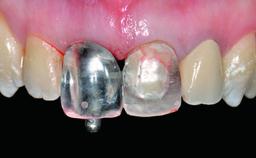

Replacement of a Perforated Upper Left Central Incisor: Early Placement of an RC Bone Level Implant

Abutment Type Customized

Prosthesis Type FDP

Retention Cemented, with prosthesis margin < 3mm submucosal Cemented, with prosthesis margin < 3mm submucosal

Provisional Implant-Supported Prosthesis Prosthodontic margin < 3 mm apical to mucosal margin Prosthodontic margin < 3 mm apical to mucosal margin